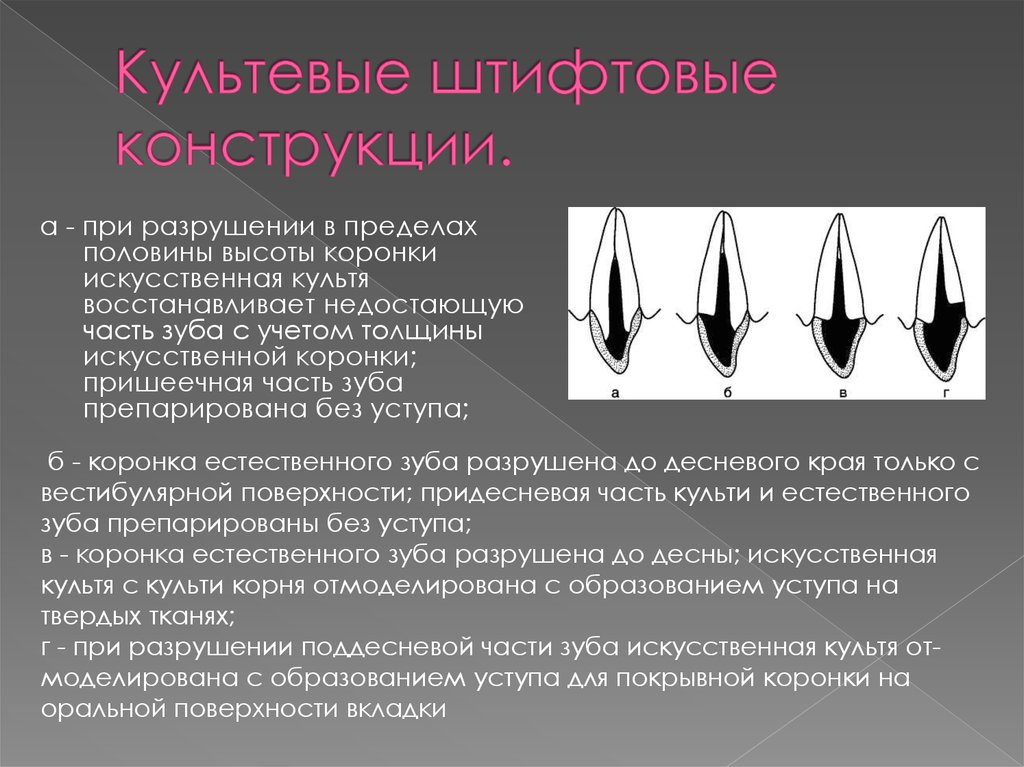

Культя зуба это

Культя зуба это 106 фото